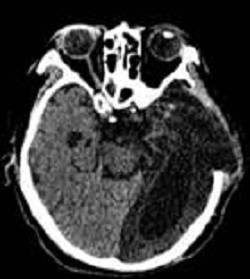

王先生7个多月前因脑外伤导致意识障碍

继发肺部感染行“气管切开术”

反复肺部感染10余次

曾先后就诊于多家医院ICU及呼吸科

血氧饱和度维持不稳,无法脱氧

转至郑州大学五附院康复医学科时

仍意识障碍气管切开状态,反复发热

痰液较多,不易咳出,鼻饲饮食

1.重症肺炎;

2.呼吸功能障碍;

经过2月的治疗,患者生命体征稳定,无明显咳嗽、咳痰,血氧饱和度明显改善,顺利脱氧,吞咽功能好转,少量饮水(5ml)无明显呛咳,双下肺湿性啰音较前减少,血红蛋白及白蛋白明显增加,营养状况较前好转。拔管各项指征达标,成功拔出气管套管。